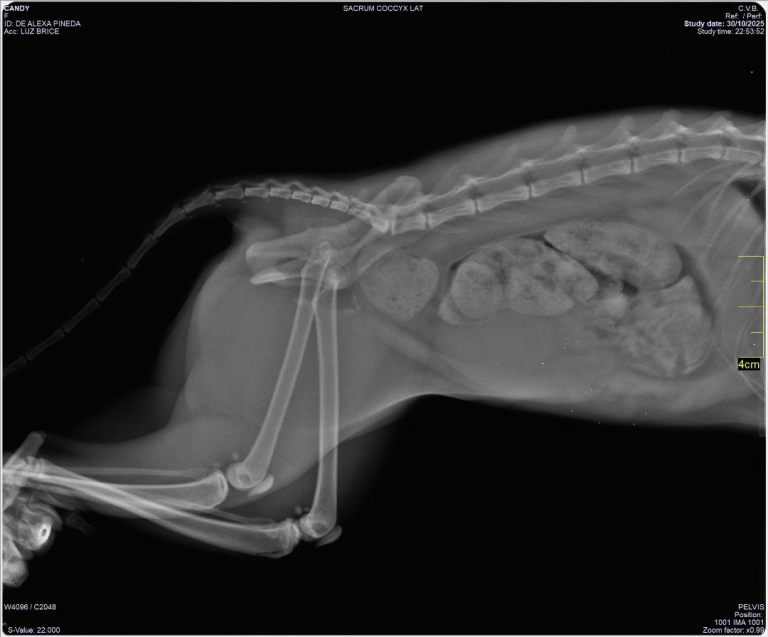

La Radiología Digital (RD) es vital para el diagnóstico oportuno, la tecnología actual ofrece una ventana de alta resolución y […]